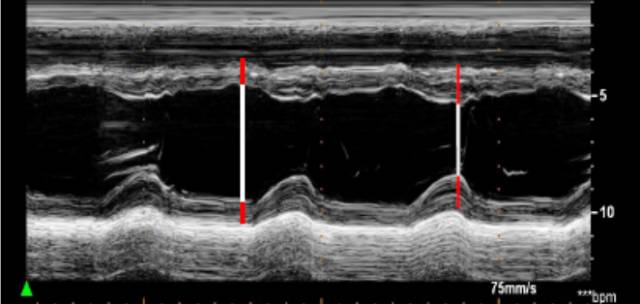

直接二维测量或在二维引导下的M-型曲线上测量。

ASE推荐于二尖瓣瓣尖水平胸骨旁短轴切面直接测量或采用M型曲线测量。M-型超声时间分辨率好。有助于帮助二维超声区分临近左室后壁的肌小梁、室间隔左室面的假腱索、室间隔右室面的调节束等结构。即使采用二维引导也可能无法保证M-型取样线完全垂直于室间隔和左心室后壁。